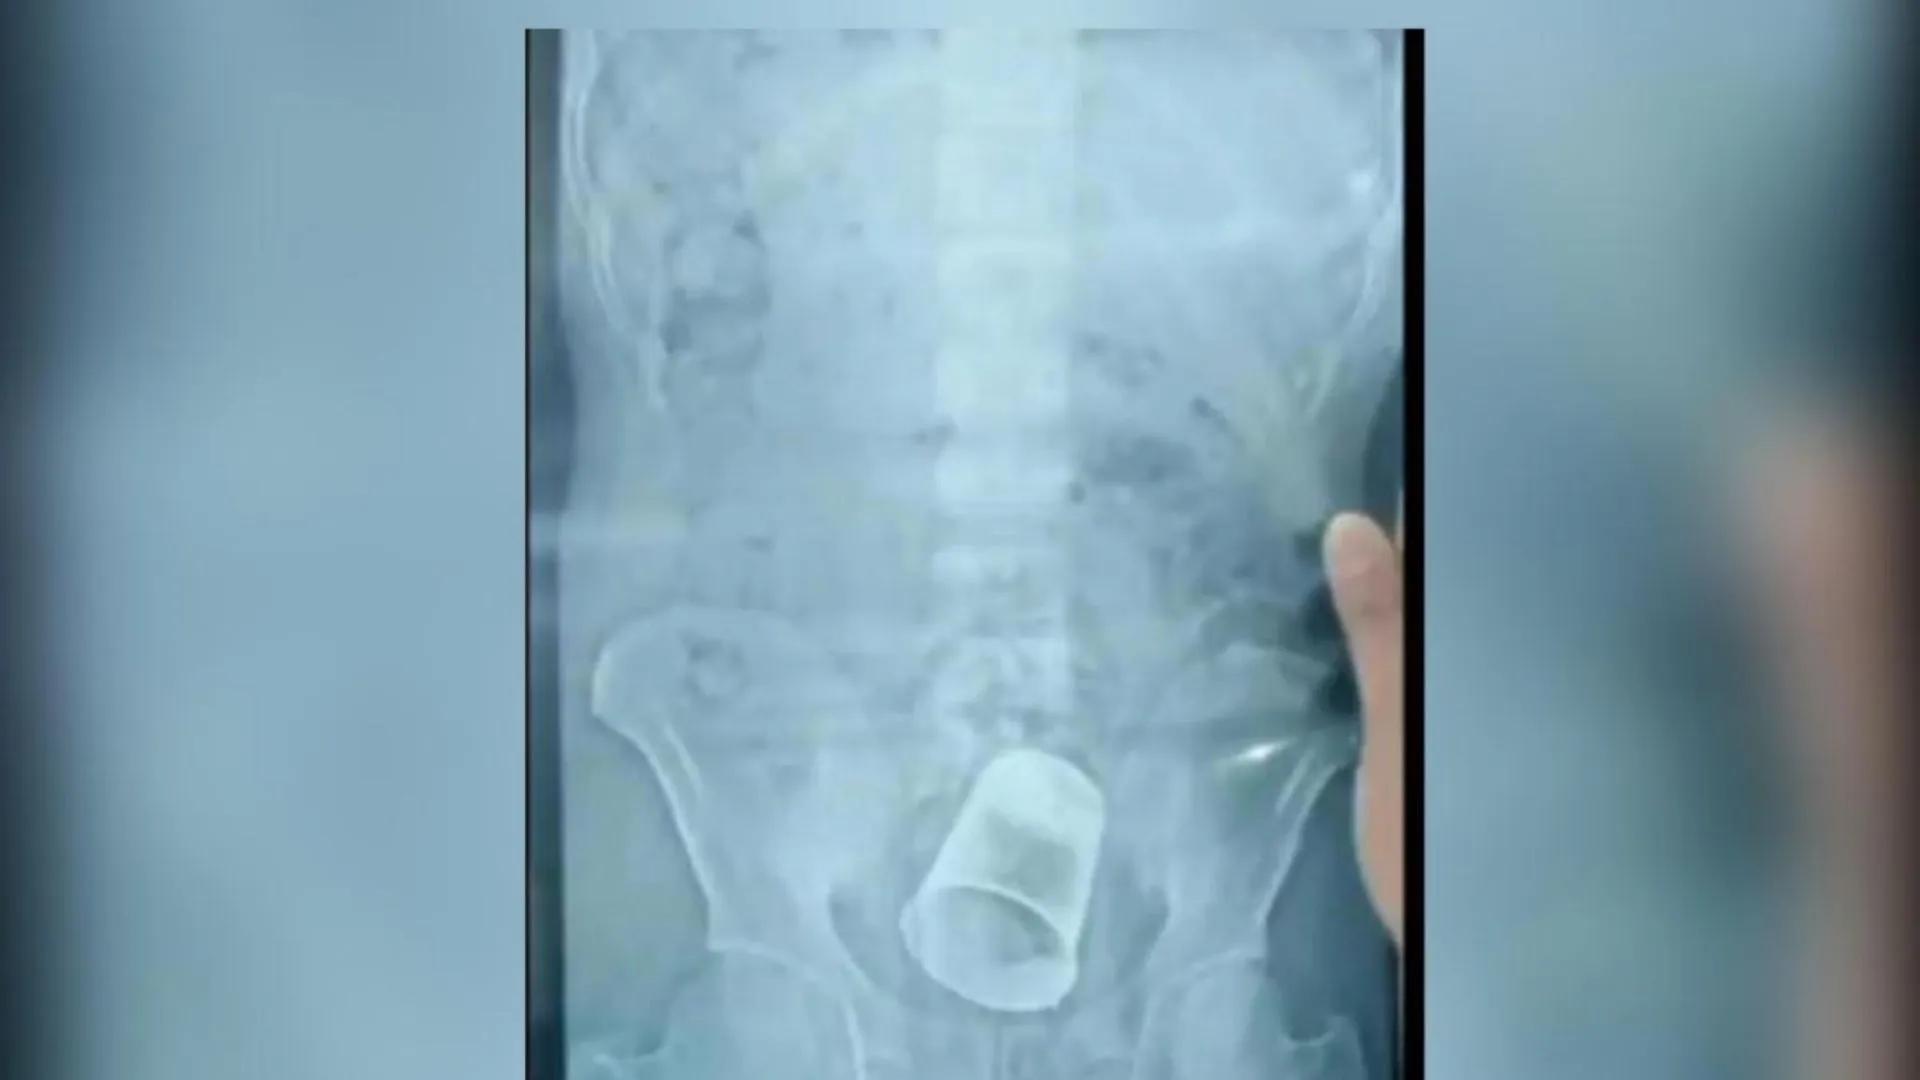

ससुराल से वापस घर जाने के बाद लगातार युवक के पेट में दर्द हो रहा था। स्थानीय डॉक्टर से इलाज के बाद भी जब नहीं ठीक हुआ तो डॉक्टरों ने उसे SKMCH रेफर कर दिया। वहा जब डॉक्टर ने उसके पेट का एक्सरे कराया तो पेट में गिलास दिखा। इसके बाद मेडिकल टीम ने एक्सरे और अन्य रिपोर्ट की जांच कर शुक्रवार को ऑपरेशन कर स्टील का गिलास निकाला। हालांकि अभी तक युवक के परिजन ने पुलिस से मामले की शिकायत नहीं की है।

इस मामले में डॉ. राजेश कुमार ने बताया कि गुरुवार की शाम साहेबगंज का एक मरीज भर्ती हुआ था, जिसके पेट में दर्द था। उसके प्राइवेट पार्ट में गिलास था। इसका पता मरीज को नहीं था। जब वह पेट दर्द की शिकायत लेकर आया तो एक्स-रे से पता चला। इसके बाद ऑपरेशन कर गिलास को निकाल दिया गया है। युवक ने बताया है कि 20 दिन पहले उसके ससुरलवालों ने उसके साथ मारपीट की थी, जिससे वह बेहोश हो गया था। इसके बाद उन्होंने प्राइवेड पार्ट में गिलास डाल दिया।

युवक ने कहा कि दूसरे दिन जब होश आया तो पेट में दर्द हो रहा था। इलाज करवाने आए तो पता चला पेट में गिलास है। पीड़ित युवक की मां का कहना है कि शादी के बाद से बहू घर नहीं आती है, इसलिए बेटा उसे बुलाने गया था तो उसके साथ मारपीट कर बेहोश कर दिया। इसके बाद जब उसके पेट में दर्द हुआ तो आज एसकेएमसीएच में पहुंचा, जहां एक्सरे में जानकारी हुई है।9.jpg)

बता दें कि ऐसा ही एक मामला ओडिशा से भी बीते साल अगस्त में सामने आया था। जहां बेरहामपुर में डॉक्टरों ने सर्जरी कर एक शख्स के पेट से स्टील का गिलास निकाला था। ये गिलास आदमी की आंतों में फंसा हुआ था। घटना बेरहामपुर शहर के MKCG मेडिकल कॉलेज और अस्पताल की थी। सर्जरी से पहले शख्स के किए गए एक्स रे (X Ray) की तस्वीरें भी सामने आई थीं, जिसमें आंत में एक स्टील का गिलास साफ नजर आ रहा है।